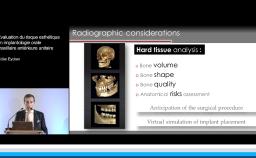

Au cours de cette présentation, le Dr Finelle nous montre tout l’intérêt du digital workflow dans une réhabilitation implantaire en secteur esthétique. Ainsi, à chaque étape de celle-ci, le numérique peut intervenir : au cours du diagnostic, de la chirurgie, de l’empreinte ou encore au cours de la réalisation prothétique.

Au travers de plusieurs cas cliniques, il nous est montré comment différents outils numériques permettent de préparer et d’obtenir une réhabilitation esthétique optimale. Au final, le digital workflow va apporter précision, prédictibilité, facilité de reproduction des formes dans la réhabilitation prothétique implantaire ; c’est également un formidable moyen de communication avec le patient.